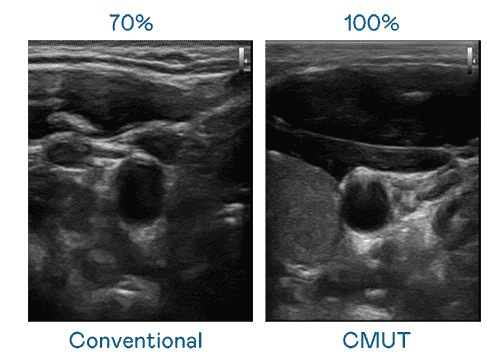

CMUT 技术是一种用电容式微机电元件来产生超音波讯号的技术。。。与传统 PZT 压电式技术相比,,,,CMUT 频宽增加 30%,,更宽频的超音波讯号让影像解析度大幅提升,,,是实现高影像品质医疗超音波扫描、、、促进精准医疗发展的关键技术。。。。

超音波影像的解析度高低,,首先取决于探头能发出的讯号频宽。。z6尊龙 CMUT 可提供高清晰的超音波讯号,,,提供高频宽、、、高灵敏度、、、、影像纹理细节更高的超音波影像,,,协助医护人员缩短影像判读时间及利用精准的医疗影像进行诊断。。。